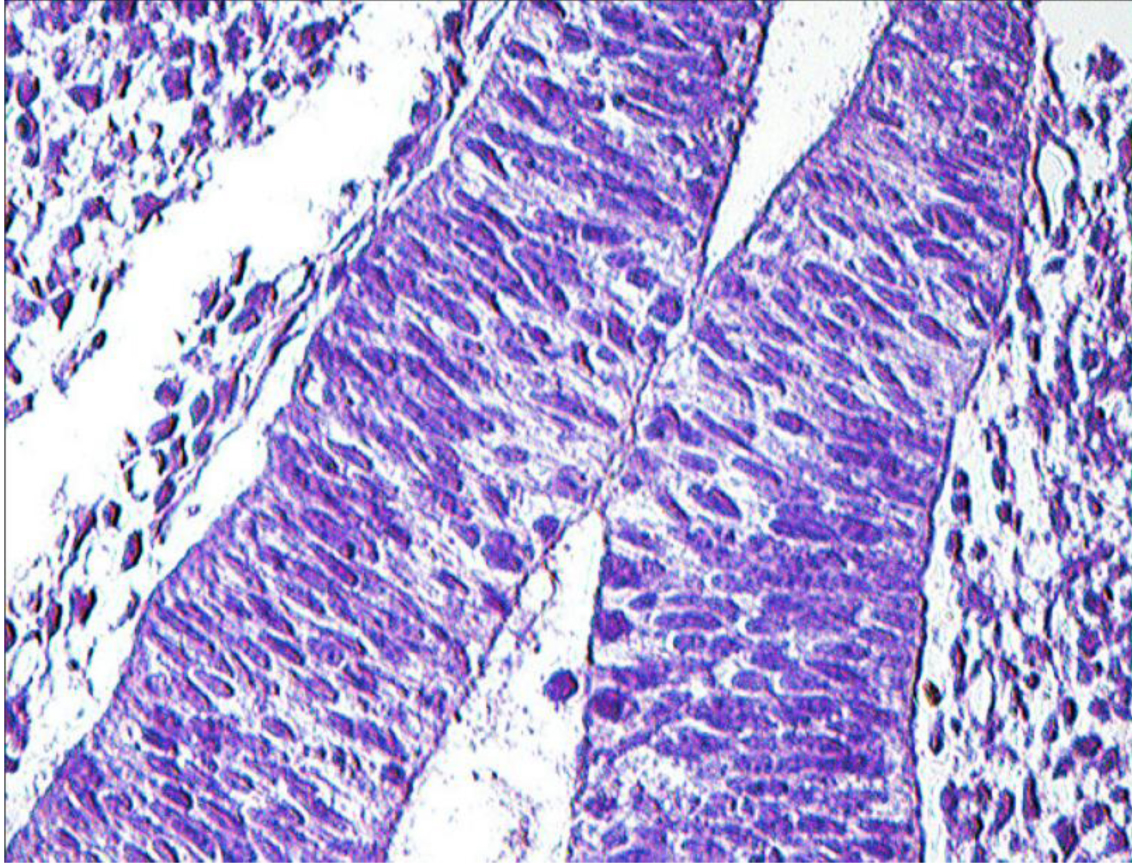

Рис. 1. Эмбрион человека. Биологический возраст 28–29 суток. Передний нейропор. Фиксация: 10%-й нейтральный формалин. Окраска: ШИК-метод по Мак-Манусу. 10 × 40

Компоненты жаберного аппарата участвуют в построении глоточной кишки и ее производных. Диссоциация хорды на уровне орофарингеальной мембраны позволило сформироваться стомодеальному карману и карману Ратке – источнику развития аденогипофиза (рис. 2).

Рис. 2. Эмбрион человека. Биологический возраст 30–32 суток: 1 – устье кармана Ратке; 2 – карман Сесселя; 3 – глоточная кишка; 4 – стенка промежуточного мозгового пузыря. Фиксация: 10%-й нейтральный формалин. Окраска: ШИК-метод по Мак-Манусу. 7 × 40